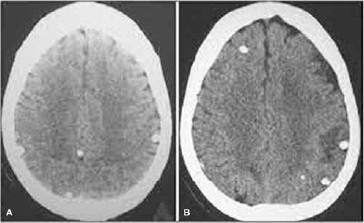

Observe a imagem a seguir.

Com base nessa imagem, o diagnóstico é: